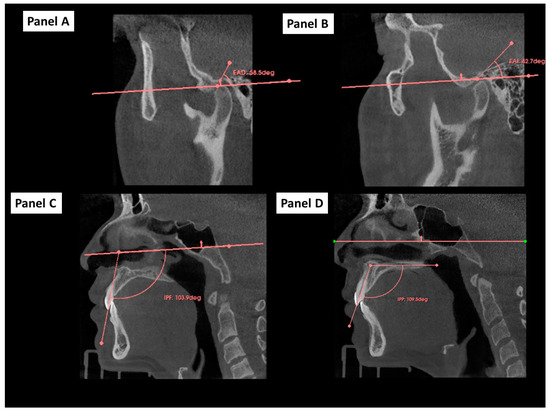

2.5. Cephalometric 2D Variables